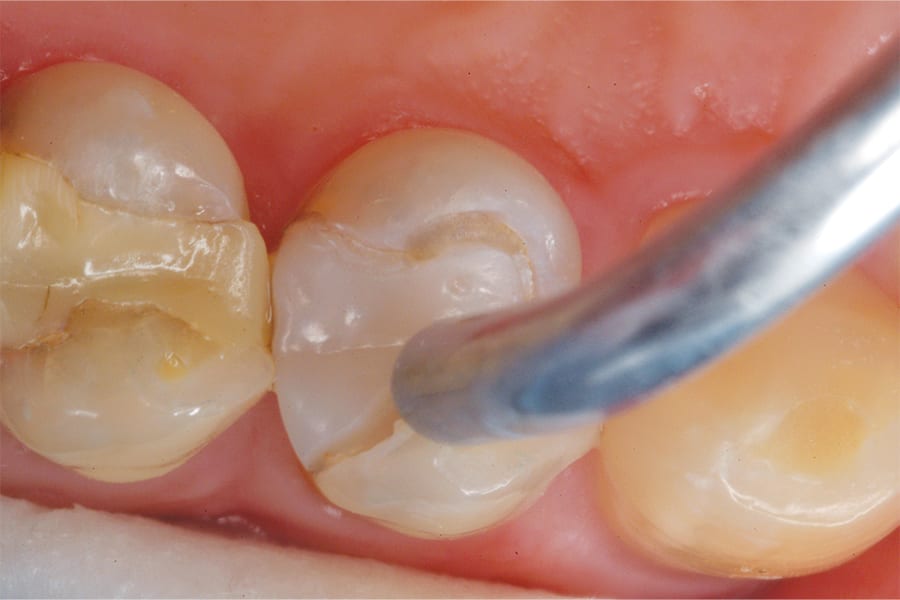

The effective repair of defective composite margins requires specialized tools and specialized materials. To begin, a high-speed, carbide bur with a very narrow width and a tapered shape designed to conservatively access pits and fissures (Fissurotomy®, SS White) was used to remove all of the decay and questionable tooth material from the perimeter of the restoration (Figure 2). This minimally invasive bur was selected because its 2.5-mm head delivers precise cuts to just beneath the dentinoenamel junction and no further. In addition, its tapered shape results in the cutting tip encountering very few dentinal tubules and helps reduce heat buildup and vibration—enhancing patient comfort and minimizing anesthesia requirements.